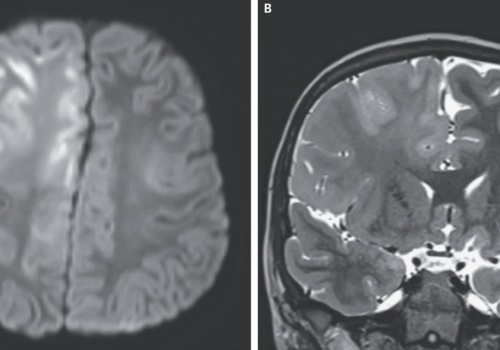

Przez lata odra była w USA chorobą praktycznie zapomnianą, bo po wprowadzeniu powszechnych szczepień w 2000 roku praktycznie ją wyeliminowano. W konsekwencji nasilania się nastrojów antyszczepionkowych i polityki administracji Trumpa, sytuacja zaczyna się jednak zmieniać i od początku 2025 roku odno...

źródło: https://geekweek.interia.pl/medycyna/news-tak-wyglada-mozg-zniszczony-przez-odre-a-wystarczylo-szczepi,nId,22604377